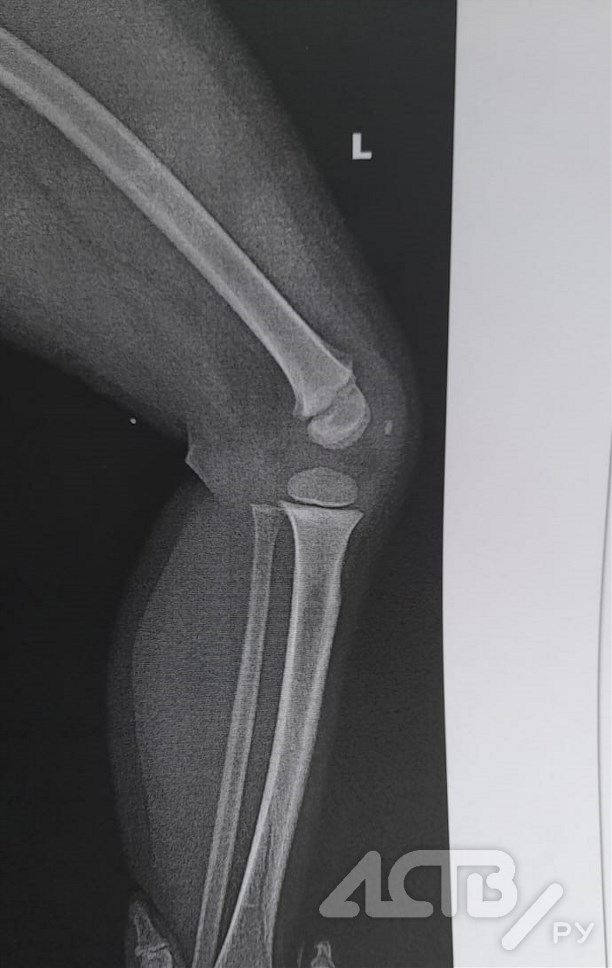

"Мне пояснили, что воспитательница не видела, как ребёнок получил травму. Сын у меня разговаривает хорошо, поэтому рассказал сам: упал, сорвавшись с борта беседки. Тут же поехали в Корсаковскую ЦРБ, где по результатам осмотра и рентгена диагностировали винтообразный перелом большеберцовой кости. Первые ночи сын не спал, очень громко кричал. Сейчас чувствует себя лучше, но вынужден постоянно лежать, а если гулять, то только коляске".

Видимо, упал сильно. Помимо травмы ноги, были также грязь и ссадины на руках", - отметила мама пострадавшего.